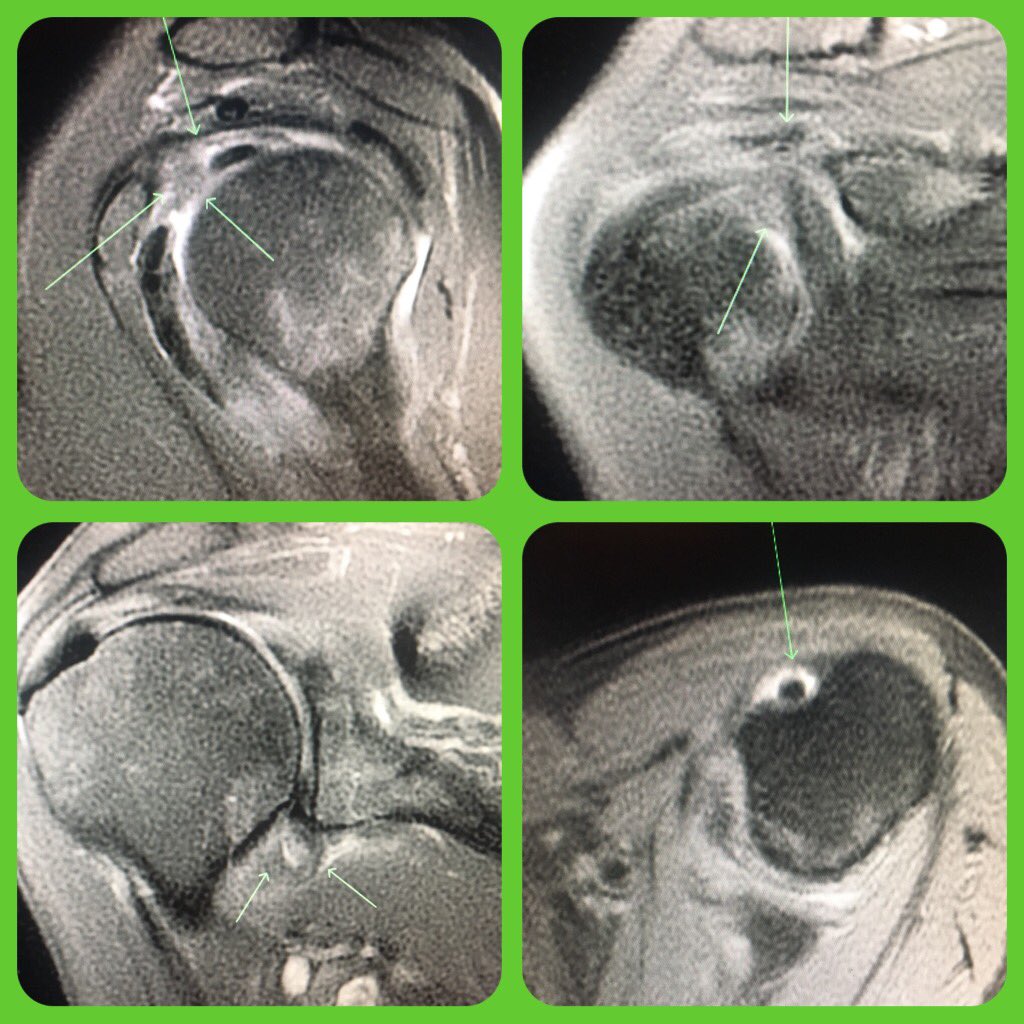

Nice example of adhesive capsulitis of the shoulder! MRI: - Synovitis at cuff interval - Edema at inferior capsule - Joint fluid filling biceps sheath, excluded from joint recesses Common clinical: - Loss of ROM, pain - Middle aged female - Following injury

Nice example of adhesive capsulitis of the shoulder!

MRI:

- Synovitis at cuff interval - Edema at inferior capsule

- Joint fluid filling biceps sheath, excluded from joint recesses

Common clinical:

- Loss of ROM, pain

- Middle aged female

- Following injury